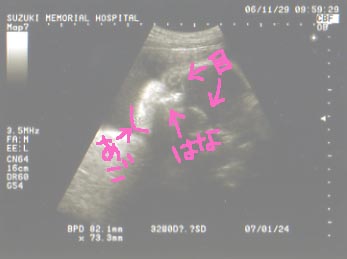

今日は顔がはっきり見えるエコー写真もらいました。

ちょっと目が不気味なんですけどね。

…ちなみに旦那さんに見せたら「??」だったので

一応解説をいれると

こんな感じです。

どっちに似ているのかは不明(当たり前)。